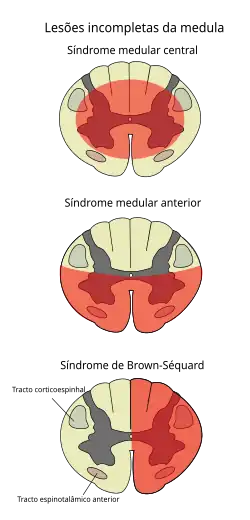

Характерный симптом — снижение или отсутствие мышечной силы в конечностях (наиболее часто вовлекаются ноги), нарушение чувствительности ниже уровня поражения спинного мозга, нарушение функции мочевого пузыря, дефекации и вегетативные нарушения. К другим симптомам относятся: симптом Лермитта[23] ,нарушение дыхания, при нарушении иннервации диафрагмы.[4] Возможно вовлечение только одной половины спинного мозга — когда на поврежденной стороне развивается паралич и нарушается ощущение вибрации и положения конечности в пространстве, а на другой стороне нарушается болевая и температурная чувствительность. Такое сочетание симптомов носит название — синдром Броун-Секара.[24][25]